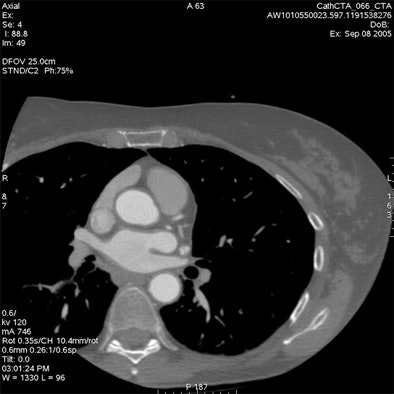

Most CT scanner manufacturers now offer bowtie filters, which reduce the maximum field-of-view (FOV) allowable while cutting the radiation dose, Budoff said.

For example, using protocol parameters of 600 mA, 120 kV, and a heart rate of 60 bpm, a small cardiac bowtie filter (standard 25-cm FOV) permits cardiac images to be acquired at dose-length product (DLP) of 474 (8.0 mSv), Budoff said. A medium bowtie filter (allowing reconstruction to 36-cm FOV) affords a dose of 791.4 DLP (13.4 mSv).

From there, expanding the FOV to the entire thorax for screening of other important findings (lung, breast, axilla, mediastinum, and spine) would actually boost the radiation dose by 67.5%, he said.

The heart fits in a 25-cm field-of-view, permitting the use of a small bowtie filter in medium-sized and sometimes even larger patients, Budoff said. "We're only worried about the heart," he said.

Of course, more anatomic coverage is often needed, Budoff said. Sometimes the radiologist needs to look for aortic dissection or pulmonary embolism, but at that point it's not a heart study.

"What I call a cardiac CT always includes the great vessels, the myocardium, the left and right atrium, and pericardium," Budoff said. "I'm never only interested in the coronary anatomy. But in cardiac CT, I'm never interested in the lung. If I'm interested in the lungs, I can do a dedicated lung scan for an additional 0.7 mSv of radiation and have it interpreted separately and done properly."